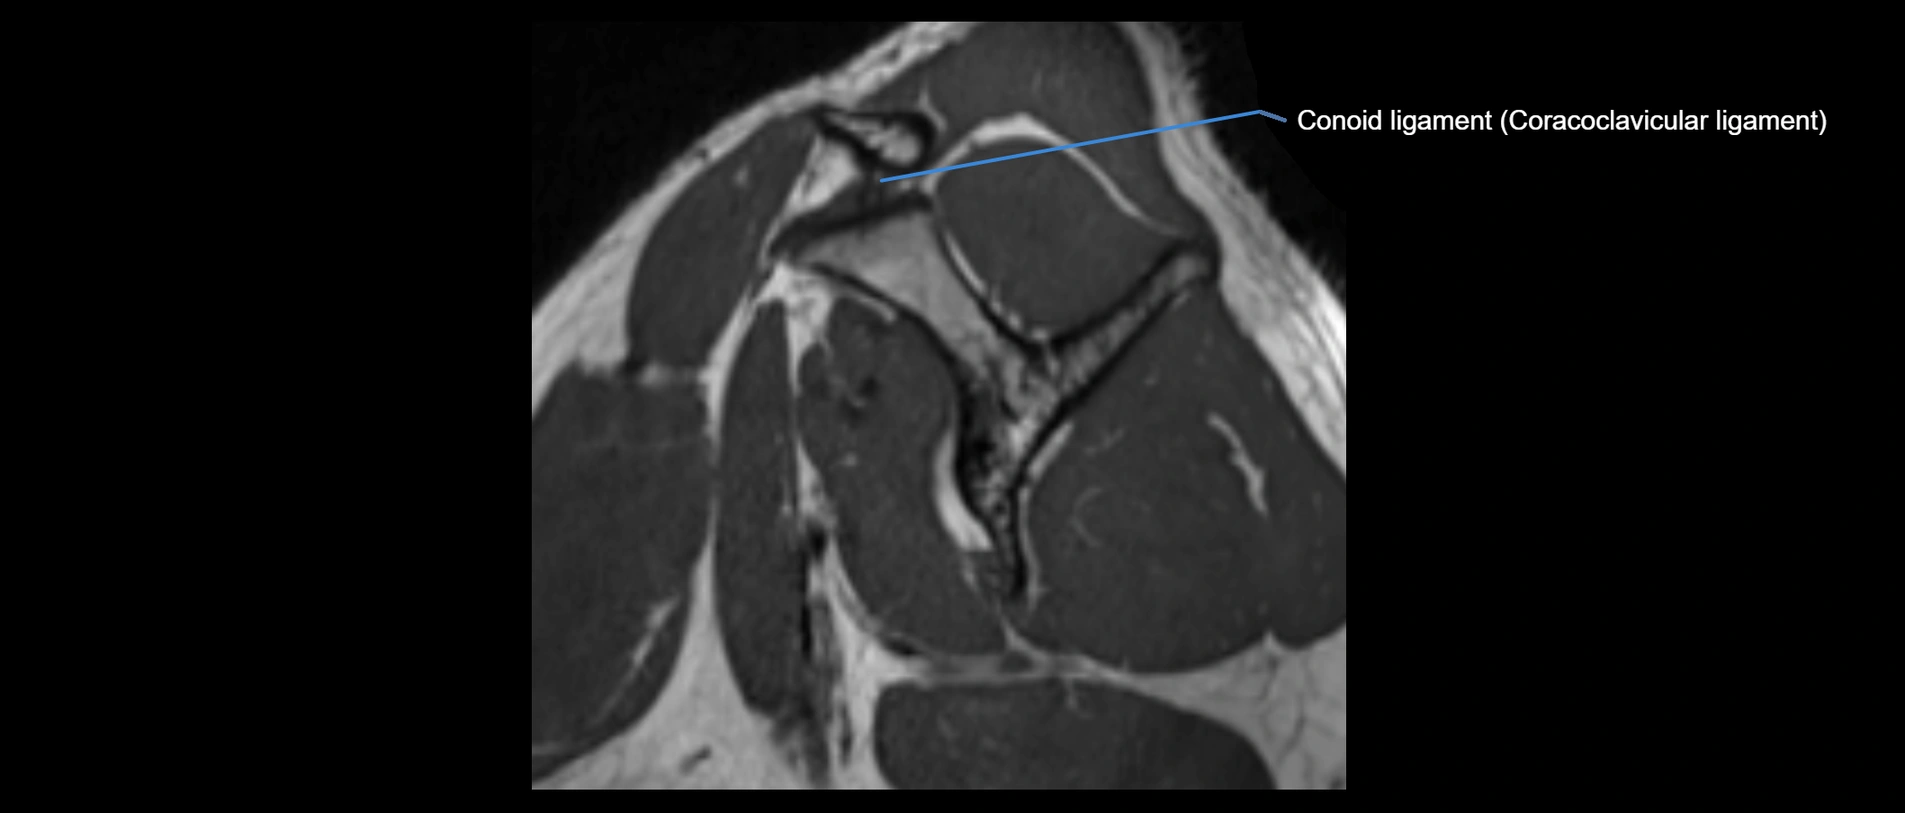

CT image

image